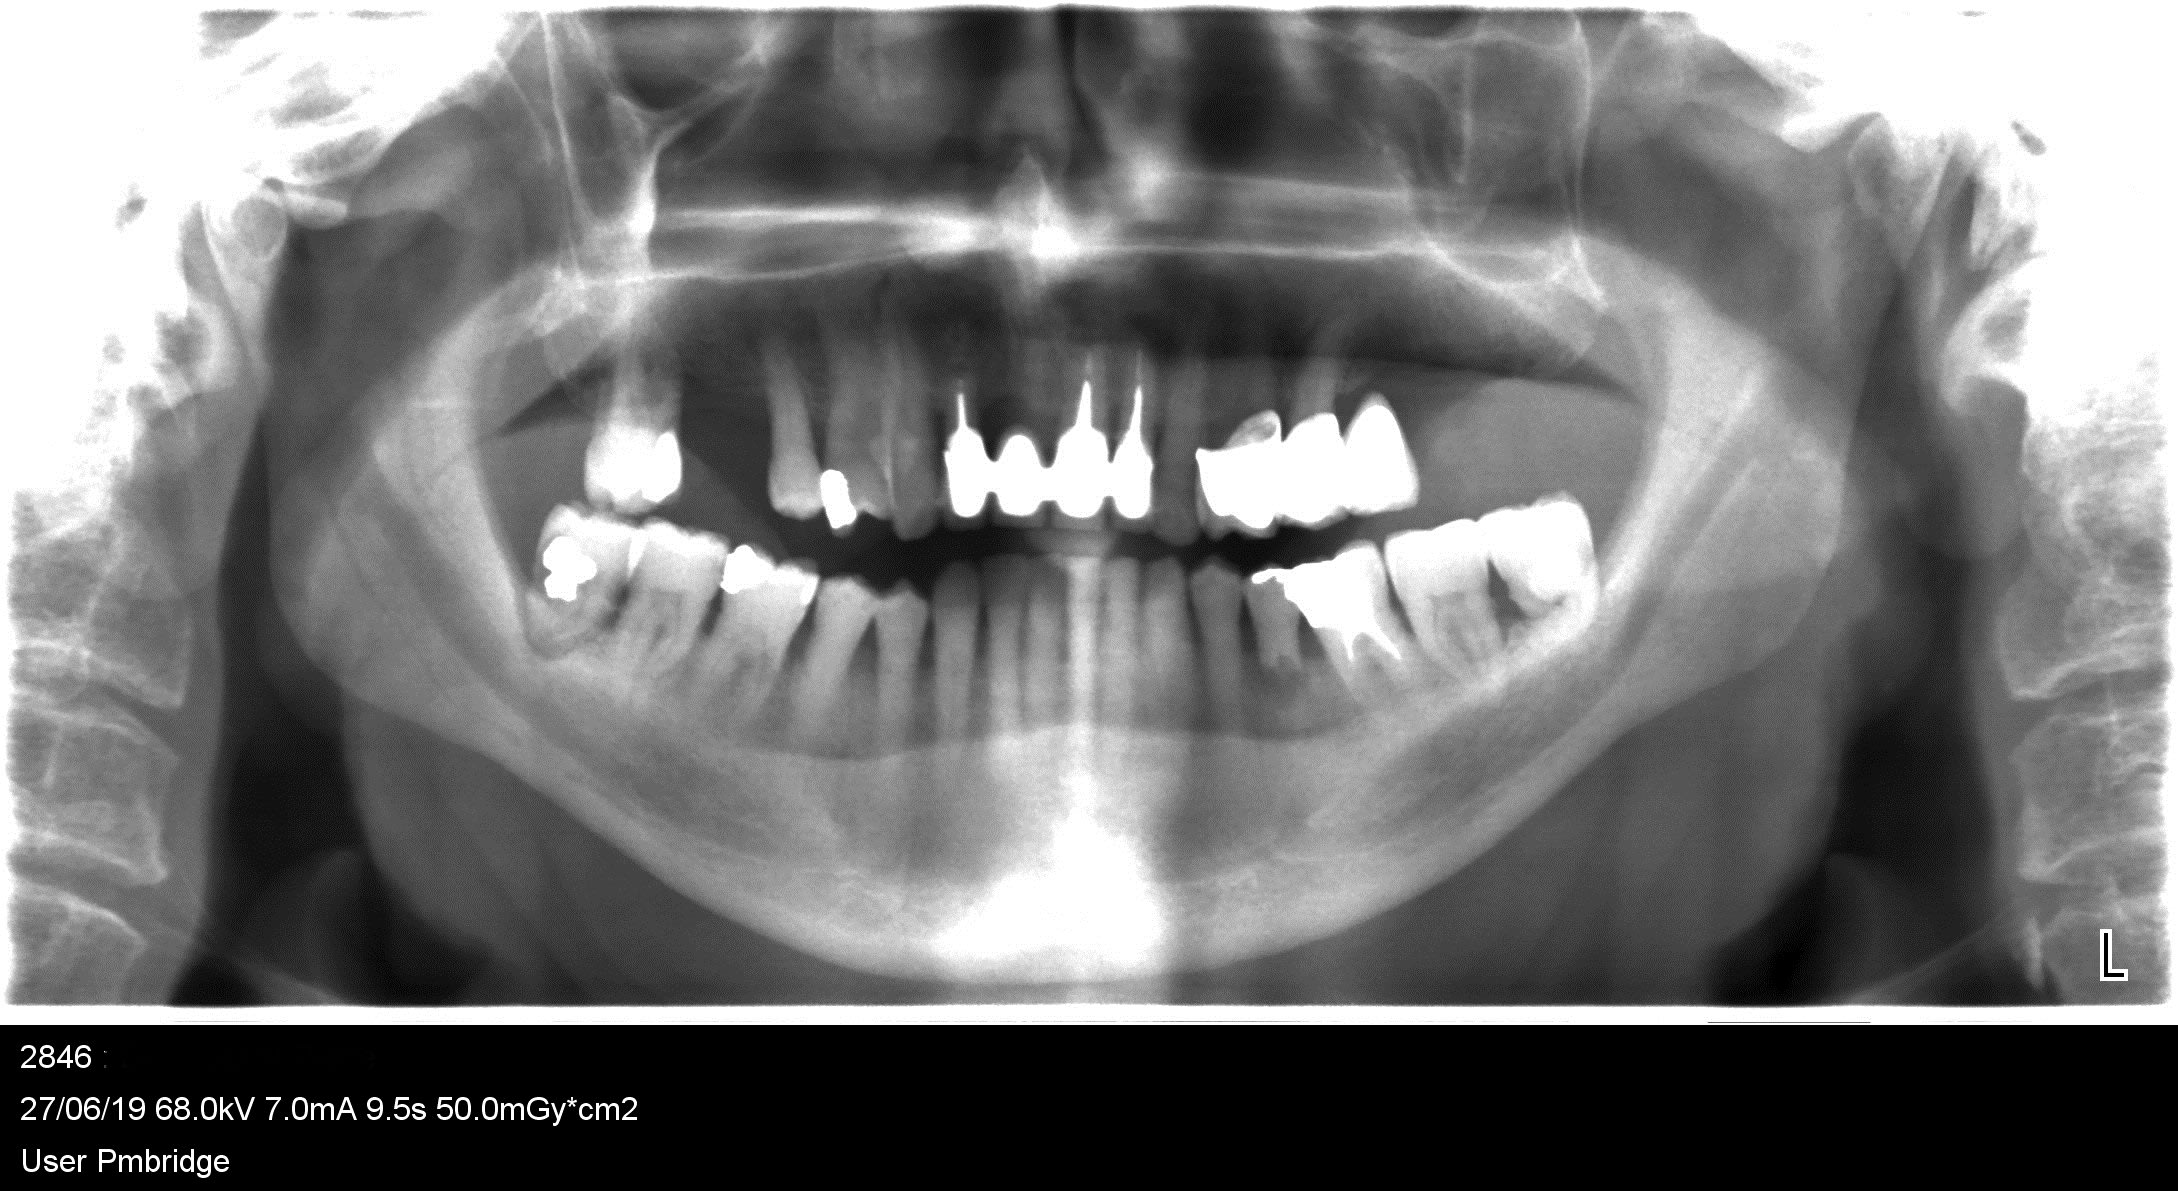

chichi

radio peropératoire

Cliché daté du 13/03...Donchico a vu juste,il est temps d'eliminer cet apex.

Sachant en avoir laissé un....pourquoi tourner autour du pot?.Ca devient dangereux pour le patient ce trajet de fusée.